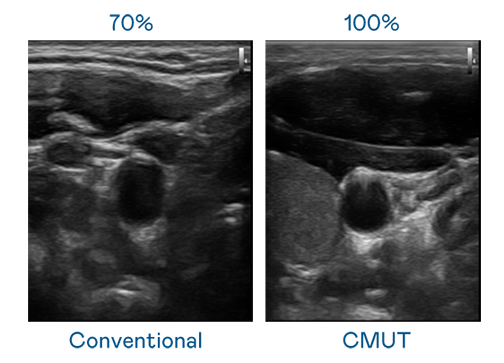

CMUT 技术是一种用电容式微机电元件来产生超音波讯号的技术。与传统 PZT 压电式技术相比,CMUT 频宽增加 30%,更宽频的超音波讯号让影像解析度大幅提升,是实现高影像品质医疗超音波扫描、促进精准医疗发展的关键技术。

大频宽带来超清晰影像

超音波影像的解析度高低,首先取决于探头能发出的讯号频宽。ag尊龙凯时 CMUT 可提供高清晰的超音波讯号,提供高频宽、高灵敏度、影像纹理细节更高的超音波影像,协助医护人员缩短影像判读时间及利用精准的医疗影像进行诊断。